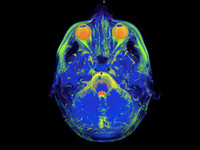

"Debemos conocer el calendario de los hemisferios cerebrales". Entrevista a Isabel Fernández del Castillo (primera parte)

Educación InfantilPara enlazar con la serie de artículos que estamos publicando con propuestas para cambiar la educación vamos a ofreceros entrevistas a expertos que nos ayudarán a entender mejor las auténticas necesidades de aprendizaje de los niños....